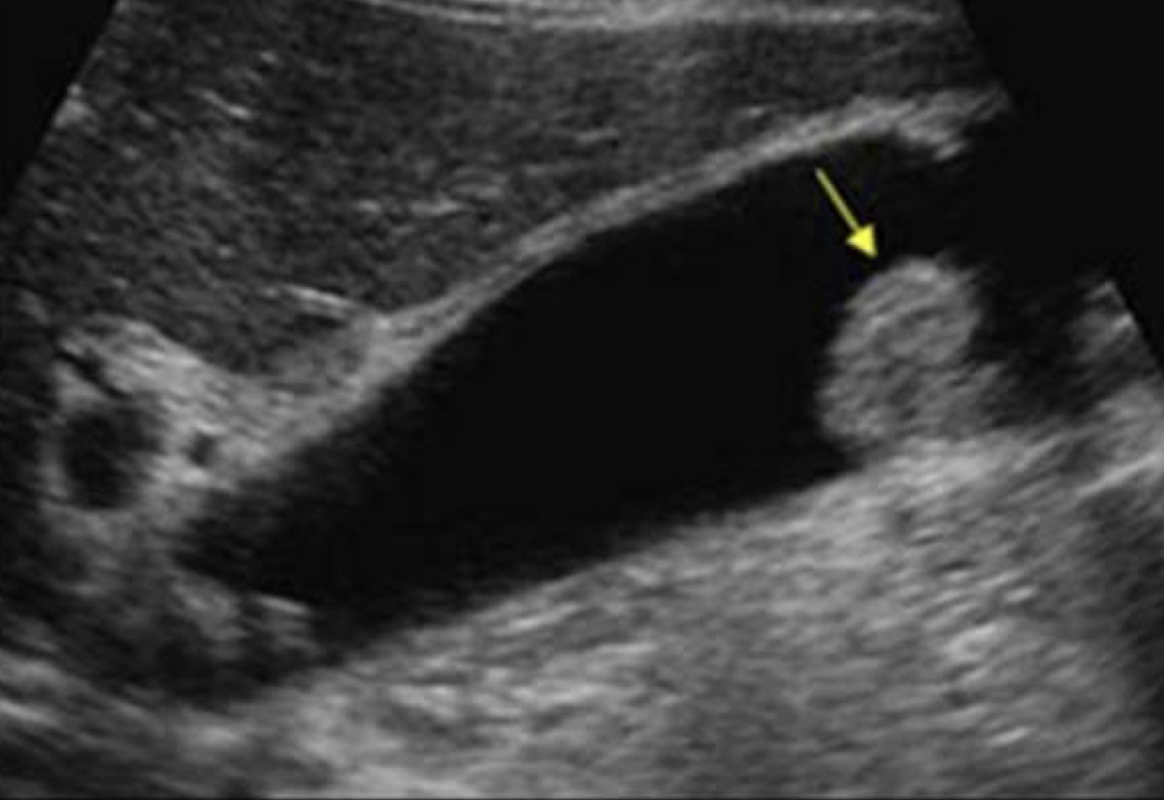

SONO: acute cholecystitis

+ Murphy’s sign

irregular wall > 3 mm

gallstones usually present

wall edema

hyperemia due to inflammation

pericholecystic fluid may be present

??

acute cholecystitis

irregular, thickened wall